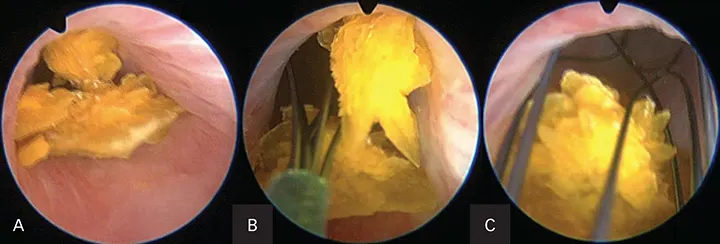

Figure 7. Endoscopic image of a calcium oxalate stone in a female dog during laser lithotripsy.

Figure 8. Endoscopic images of a dog with numerous calcium oxalate bladder and urethral stones during percutaneous cystolithotomy. Embedded stones within the urethral lumen (A). Stone basket entrapping the stones (B). Stone basket removing the stones (C).